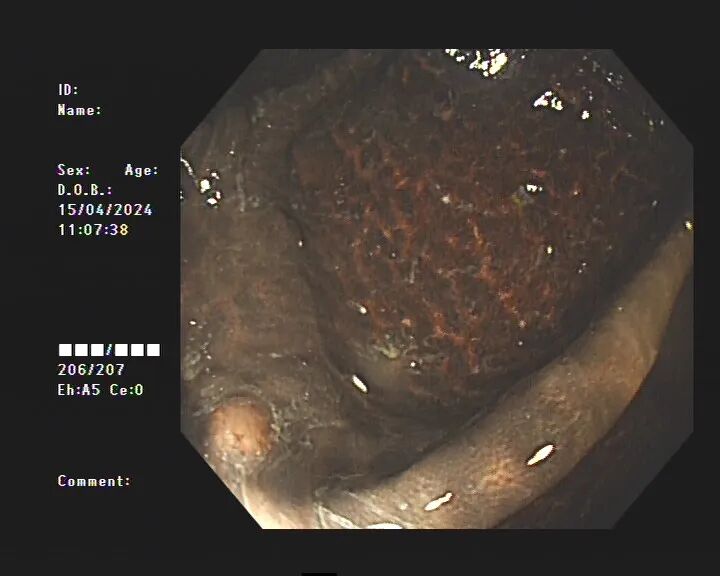

不查不知道,一查嚇一跳!患者整條大腸內(nèi)壁呈現(xiàn)棕黑色蛇皮樣的改變,黑色素沉著明顯,診斷為“結(jié)腸黑變病”,若繼續(xù)發(fā)展,有癌變的可能。

腸子變“豹紋”,一點(diǎn)也不罕見

據(jù)醫(yī)生介紹,臨床上許多患者自行口服藥物后篩查腸鏡均有不同程度的結(jié)腸黑變病。正常的結(jié)腸黏膜就像我們的口腔黏膜一樣,是淡紅色的,看起來光滑平坦,黏膜表面的小血管紋理清晰可見。而結(jié)腸黑變病的腸黏膜色澤呈現(xiàn)棕色、褐色,有豹紋或者蛇皮一樣的條狀紋,嚴(yán)重的甚至?xí)兂珊谏?/span>

結(jié)腸黑變病患者

結(jié)腸黑變病是因?yàn)榻Y(jié)腸壁的吞噬細(xì)胞吞噬了褐色素樣物質(zhì),導(dǎo)致腸壁色素沉著。通俗點(diǎn)說,就是大腸吃多了色素,就變成了黑腸。此外,直腸前突、腸套疊、潰瘍性結(jié)腸炎等其他疾病也可能導(dǎo)致黑變病。